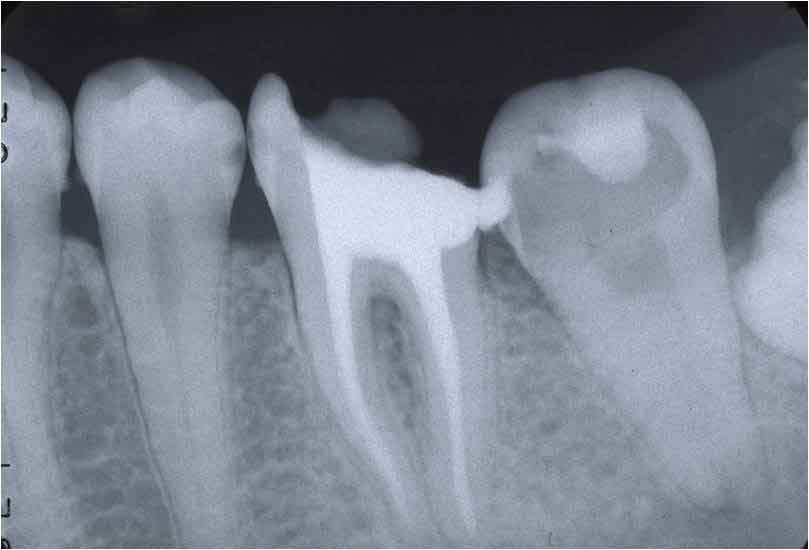

これが、根管が大きく(若年者であることが多い)、それも弯曲しているとなると、話がかわります。

根管が大きい=象牙質が薄い

という条件で、必要十分な拡大・形成を行い、歯根破折を起こさないようにできるだけ長く延命させていくということは、ストレートな根管であれば、慎重にファイルサイズを上げていくことで達成は可能だと思います。

一方、「ファイルサイズを上げる」 ということは 「ファイルのしなりがなくなる」 ということを意味するため、弯曲根管においては、通常の方法で治療を進めて行くに伴って、その弯曲部を無意識に、不用意につぶしていくことになります。

この結果、歯の脆弱化が進み、さらに抗原性の物質を取り残す可能性がある。

そこそこ細くて弯曲している根管より遙かに難しいのが、写真のような「太くて弯曲している根管」なのです。